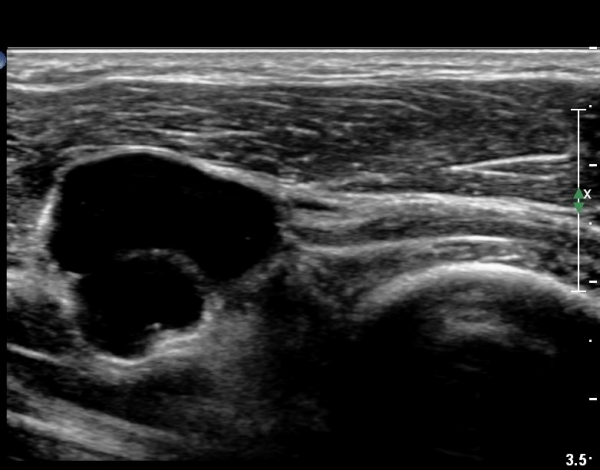

ŽÃËÀÚ¸¦ ¾à°£ ¸»´ÜÀ¸·Î À̵¿ÇÏ´Ï(¿ä°ñµÎ ºÎÀ§) Å« ³¶Á¾ÀÌ º¸ÀÌ°í ³¶Á¾ÀÇ ¿ÜÃø¿¡ Èİñ°£½Å°æÀÇ ¾Ð¹ÚÀÌ °üÂûµÈ´Ù(»çÁø 2). ³¶Á¾Àº ¿ä°ñµÎ¿¡¼­ ¿ä°ñºÎÀ§±îÁö À§Ä¡ÇØ ÀÖ´Ù(»çÁø 3)